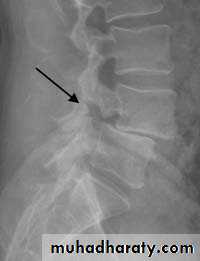

X-ray:Lateral views show the forward shift of the vertebra above on the vertebra below.

The gap in the pars interarticularis is best seen in the oblique views.

CT-scan and MRI are helpful.

L4

L3

L5

L4L5

S1